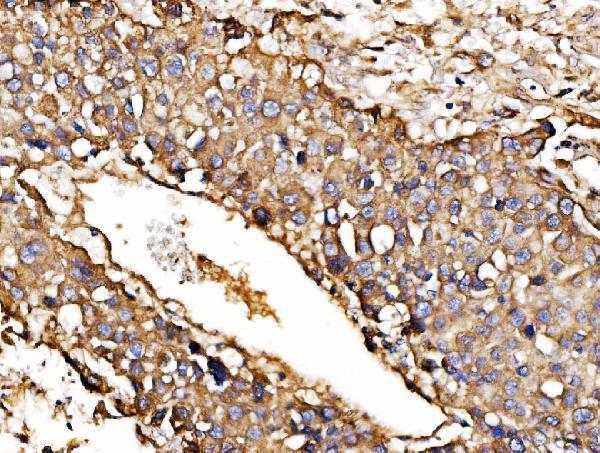

IHC analysis of ORP150/HYOU1 using anti-ORP150/HYOU1 antibody (A04934-2).

ORP150/HYOU1 was detected in a paraffin-embedded section of human gall bladder adenosquamous carcinoma tissue. Heat mediated antigen retrieval was performed in EDTA buffer (pH 8.0, epitope retrieval solution). The tissue section was blocked with 10% goat serum. The tissue section was then incubated with 2 μg/ml rabbit anti-ORP150/HYOU1 Antibody (A04934-2) overnight at 4°C. Biotinylated goat anti-rabbit IgG was used as secondary antibody and incubated for 30 minutes at 37°C. The tissue section was developed using Strepavidin-Biotin-Complex (SABC) (Catalog # SA1022) with DAB as the chromogen.